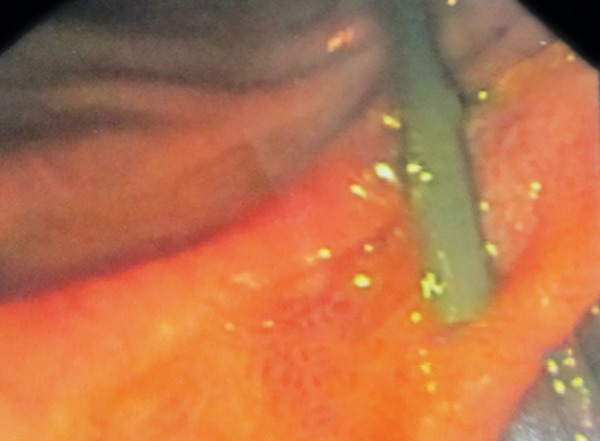

A 10-year-old girl was admitted in a private hospital for an acute abdomen. She presented with complaints of abdominal pain, distention, and fever. Preoperative ultrasound was suggestive of free fluid. Intraoperatively, there was bile in the peritoneal cavity, no bowel perforation and a rent in CBD, suggestive of biliary tract perforation. A drain was kept in the Morrison’s pouch, and she was referred to our institute for further management. At admission, the patient was stable in regard to hemodynamical parameters. The draining output was approximately 200 to 300 mL of bile per day. Contrast enhanced computed tomography (CECT) scan suggested discontinuity in the medial wall of suprapancreatic CBD extending proximally for a length of approximately 1.4 cm with an ill-defined collection in the Morrison’s pouch and mild free fluid in the peritoneal cavity (Fig. 1). Endoscopic retrograde cholangiopancreatography revealed a leak from CBD just below the insertion of cystic duct (Figs 2 and 3), and a 7 French stent was inserted with the tip beyond the leak. The abdominal draining was stopped and removed. The patient was gradually shifted to oral diet. She was discharged after 8 days, and her stent was removed after 8 weeks. She is doing well on follow-up.